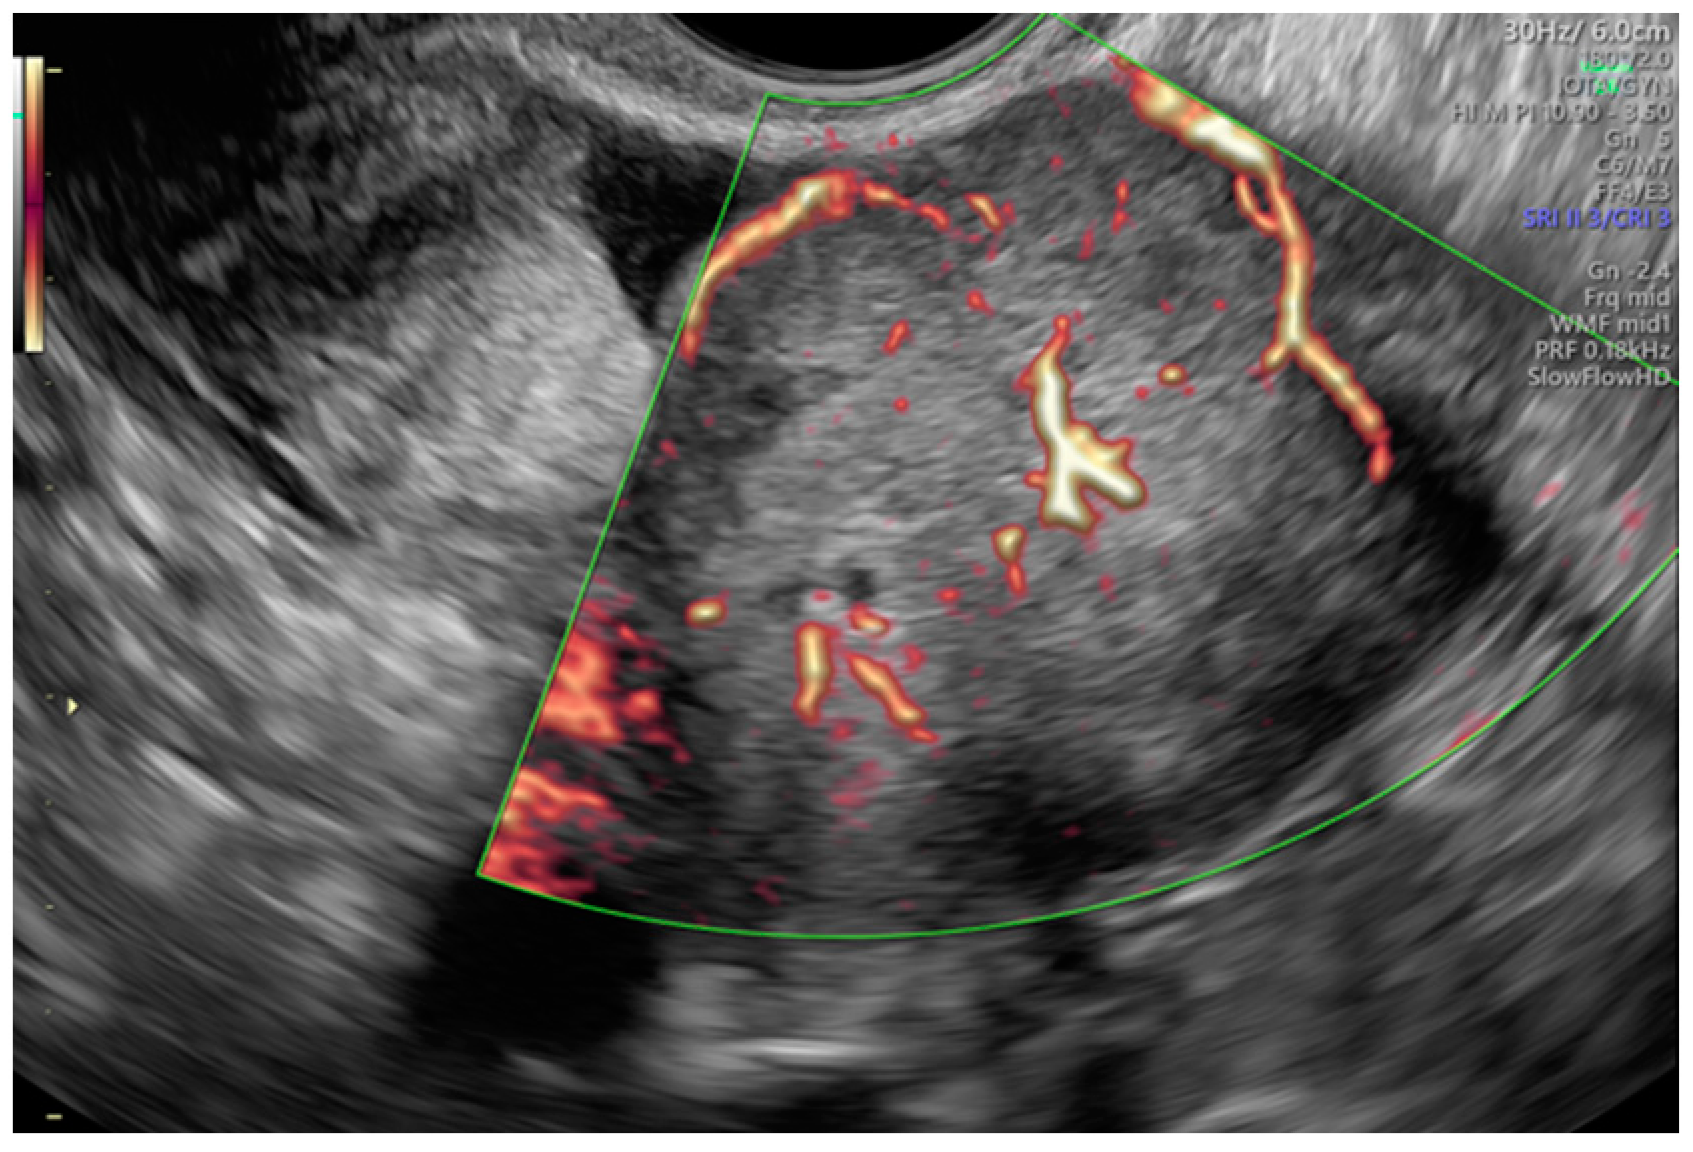

- Koneczny, J.; Czekierdowski, A.; Florczak, M.; Poziemski, P.; Stachowicz, N.; Borowski, D. The use of sonographic subjective tumor assessment, IOTA logistic regression model 1, IOTA Simple Rules and GI-RADS system in the preoperative prediction of malignancy in women with adnexal masses. Ginekol. Polska 2017, 88, 647–653. [Google Scholar] [CrossRef] [PubMed]